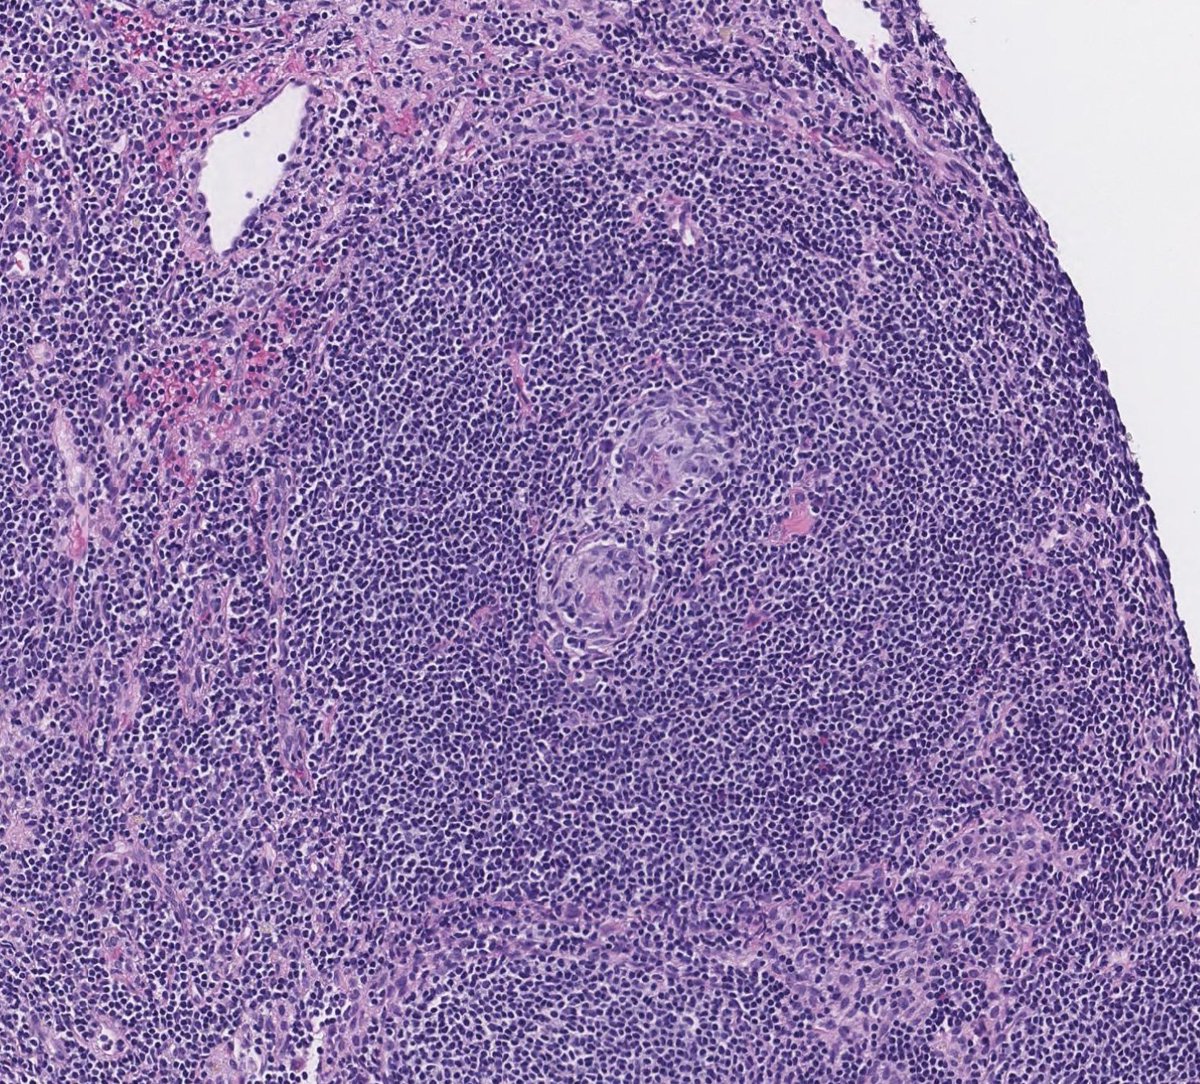

Couldn't be more excited to announce the launch of pathlibrary.com, the virtual slide site I wish had existed during my pathology residency. You can:

- See annotated histologic features